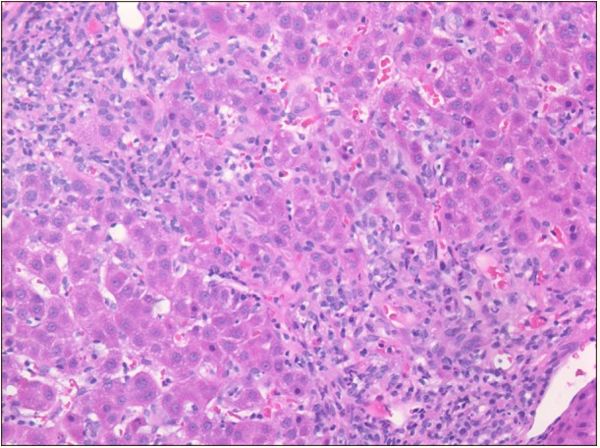

腹部超声多普勒超声检查:没有发现肝脏或胆道异常,但有轻微的脾肿大。肝脏活组织显示明显的玫瑰花结,浆细胞增多,窦状隙成熟淋巴细胞轻微增加,2期门静脉周围纤维化,无桥接或肝硬化结节,无嗜酸性粒细胞存在,无可染色铁、铜或A1AT小球。这些组织学发现与中度至重度急性慢性肝炎(总体3至4级)一致,提示自身免疫性肝炎。根据这些发现和整体临床表现,患者被诊断为继发于米诺环素的药物诱导的自身免疫性肝炎。

图1玫瑰花结和少量窦状成熟淋巴细胞